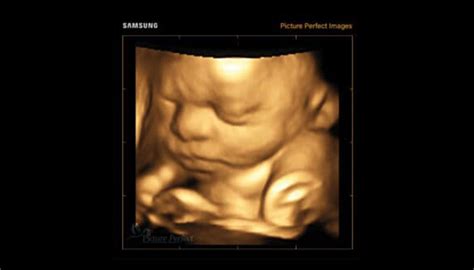

Ecografia

Ecografia este o metodă non-invazivă și una dintre cele mai comune modalități de a afla sexul copilului. De obicei, aceasta se efectuează între săptămânile 18 și 22 de sarcină, când organele genitale ale fătului sunt suficient de dezvoltate pentru a fi vizibile. Acuratețea ecografiei pentru identificarea sexului este de 80-90% după săptămâna a 12-a de sarcină, în funcție de experiența medicului și calitatea aparaturii. Uneori, poziția fătului poate împiedica vizualizarea clară a organelor genitale, necesitând o ecografie repetată.